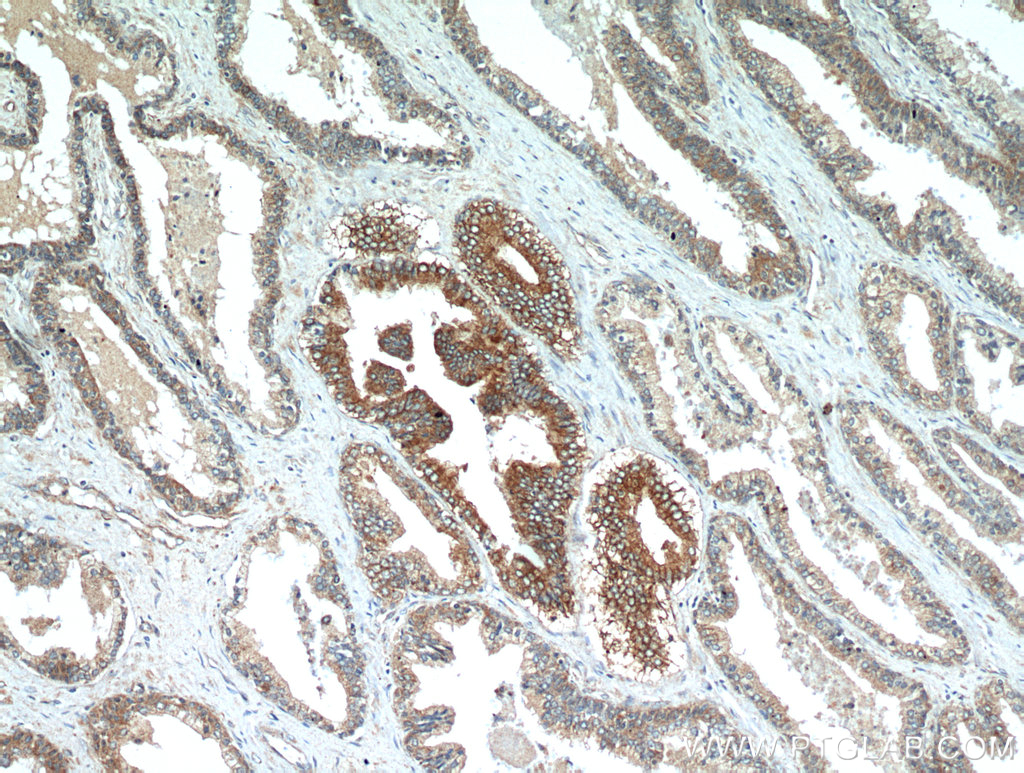

発現

ヒトのNEDD4L遺伝子は染色体上18q12.31に位置し、38個のエクソンからなり、複数のスプライスバリアントが転写される。脳、肺、腎臓で発現するタンパク質はC2ドメインを含んでいる。NEDD4Lには3つの主要なアイソフォームが存在する。アイソフォームIはエクソン1の開始コドンから始まる新奇C2ドメインを含む。アイソフォームIIは保存された完全なC2ドメインを含み、アイソフォーム1の開始コドンよりも上流の代替的開始コドンから始まる。アイソフォームIIIはエクソン2a-3のスプライシングのためC2ドメインを含まない。アイソフォームIは腎臓と副腎で多く発現している一方、アイソフォームIIは肺で支配的ある。NEDD4-2特異的抗体はほとんどの組織で110-115 kDaの2種類を認識するが、そのうちの1つは組織によって大きさが異なる。